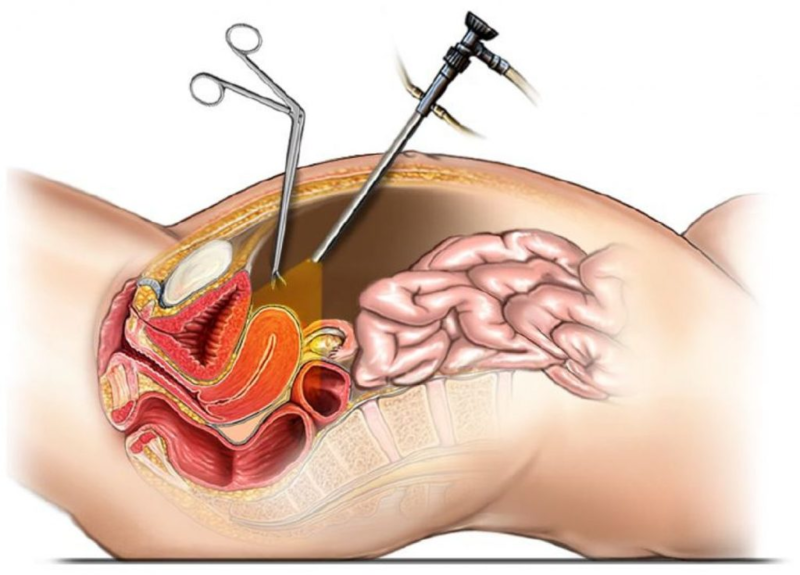

Современные методы лапаротомии и миомэктомии